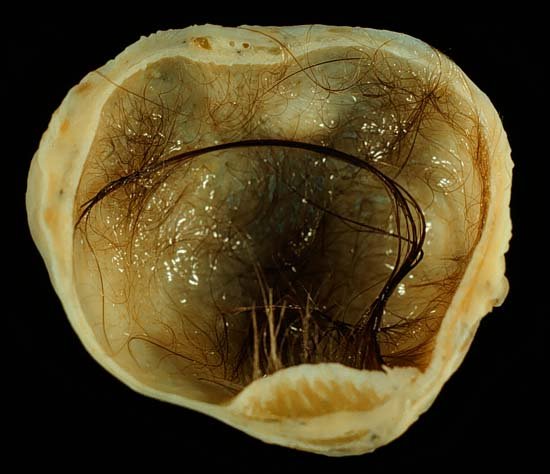

When she woke up from the anesthesia, the doctors had news. Her mom was there to capture the moment Stuthers heard that what was removed from her body was no normal ovarian cyst. It was a teratoma—a unique kind of tumor that grows from germ cells (cells that eventually become sperm or, in Stuthers’ case, eggs). Because of their origin, teratomas frequently grow hair and even teeth, along with various kinds of tissue. The teratoma inside Stuthers’ ovary had all that, and more… The surgeons even thought Stuther’s teratoma may have had an eyeball! (Later testing ruled this out… close call!)

Mostly, people just wanted to know if they could see a picture of the actual teratoma. Stuthers did eventually show a photo briefly in a follow up video, but luckily for us, we can get a better look at these things through a plethora of high-res online images.

Ready? If you’re squeamish, you might want to look away now.

(Sorry, one more photo incoming.)